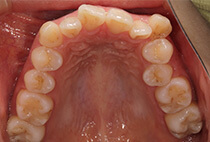

治療前